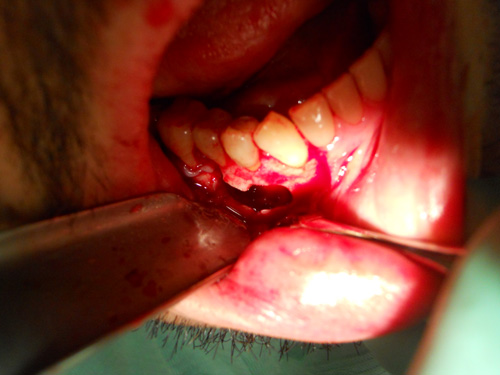

Presentazione del Caso:

La paziente si presenta alla mia attenzione in seguito al ripetuto insucesso di un perno-moncone diretto effettuato da un collega carico di 21. Il problema era la ripetuta decementazione.

Probabilmente e poi in seguito confermato siamo davanti ad una frattura della radice di 21. D'accordo con la paziente si decide di effettuare un impianto post-estrattivo a carico immediato in posizione 21. In questa seduta si prende un'improta dell'arcata per l'allestimento del provvisorio in resina.

(Intervento e foto eseguiti da me in 1h e 15min)